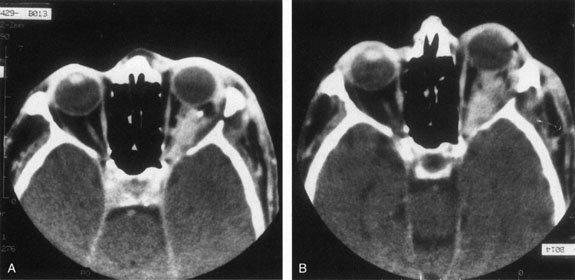

Investigations

If NFM is suspected, MRI should be ordered of the orbits and brain to exclude noncontiguous intracranial anomalies.93 Magnetic resonance imaging demonstrates the dilated cystic spaces with either a hypointense (lymphatic cyst) or hyperintense (hemorrhagic cyst) signal on T1-weighted images, and a hyperintense signal on T2-weighted images (Fig. 10, A&B).94Layering may be seen within the cysts if there has been a recent hemorrhage leaving unresorbed blood. The CT scans of patients with a deep NFM show low-density, poorly defined masses behind the orbital septum in the extraconal and intraconal spaces, which may indent the globe.3 Calcification within the mass (Fig. 11) and inhomogeneous enhancement of the rim and focal areas within the lesion may be seen that corresponds to abnormal endothelially lined channels.3 Enlargement of the bony orbit can occur, particularly with combined lesions.3,89 If the diagnosis is still unclear, ultrasonography can be performed. A cystic orbital mass is seen on B-scan. A-scan shows features of a solid, cellular tumor: low reflectivity, regular homogeneous internal structure, and marked sound attenuation through the mass.3,89 Standard pulsed Doppler ultrasound confirms no intrinsic flow within the lesions.

Fig. 10. A and B. No flow malformation of the orbit. Sagittal magnetic resonance imaging showing dilated cystic spaces hypointense to muscle on T1-weighted images (A) and hyperintense to muscle on T2-weighted images (B).